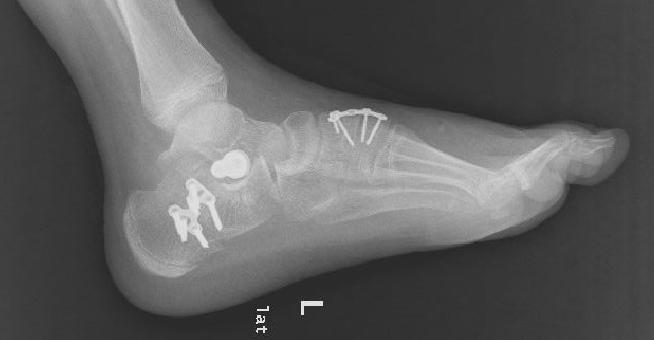

上图为患者扁平足术后影像资料